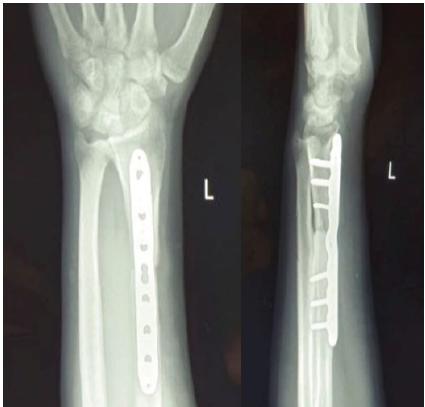

A representative example of Case 1 is illustrated in Figures 1–6. The preoperative radiograph is shown in Figure 1, while Figure 2 demonstrates the MRI findings confirming avascular necrosis of the lunate. Figures 3–5 depict the immediate postoperative radiographs and sequential follow-up images up to 1 year. Figure 6 shows the final clinical photograph, demonstrating a good functional outcome.

Figure 5: Follow-up radiographs at 12 months (anteroposterior and lateral views) demonstrate good fixation, evidence of lunate unloading, and satisfactory healing with bony union.

Figure 6: At 12-month follow-up, the patient demonstrated well-preserved wrist function, with extension of 65° and flexion of 60°, and grip strength reaching 80% of the contralateral side. Radiographs confirmed stable fixation, effective lunate unloading, and complete bony union, correlating with the excellent clinical recovery.